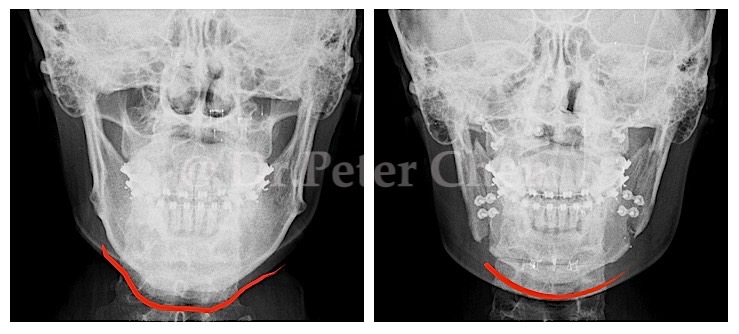

有些下顎骨突出的案例,從 X ray 上 會發現下顎骨前端(Menton)特別會突出一塊,

在手術設計上,除了利用正顎手術將下顎骨退後,最好同時將下顎骨前端的骨骼重新雕塑,才能達到理想的效果。

療程效果因人而異,上圖為該案例實際術後成效